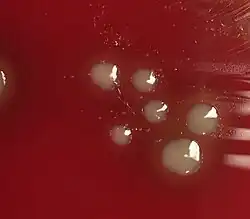

| H. influenzae on a chocolate agar plate | |

Bacterial culture of H. influenzae is performed on agar plates. The strongest growth is seen on chocolate agar at 37 °C in a CO2-enriched incubator.[33] The ideal CO2 concentration for the culture is ~5%.[34] However adequate growth is often seen on brain-heart infusion agar supplemented with hemin and nicotinamide adenine dinucleotide (NAD)

Colonies of H. influenzae appear as convex, smooth, pale, grey, or transparent colonies with a mild odor.[34] H. influenzae will only grow on blood agar if other bacteria are present to release these factors from the red blood cells, forming 'satellite' colonies around these bacteria. For example, H. influenzae will grow in the hemolytic zone of Staphylococcus aureus on blood agar plates; the hemolysis of cells by S. aureus releases NAD which is needed for its growth. H. influenzae will not grow outside the hemolytic zone of S. aureus due to the lack of nutrients in these areas.[35]